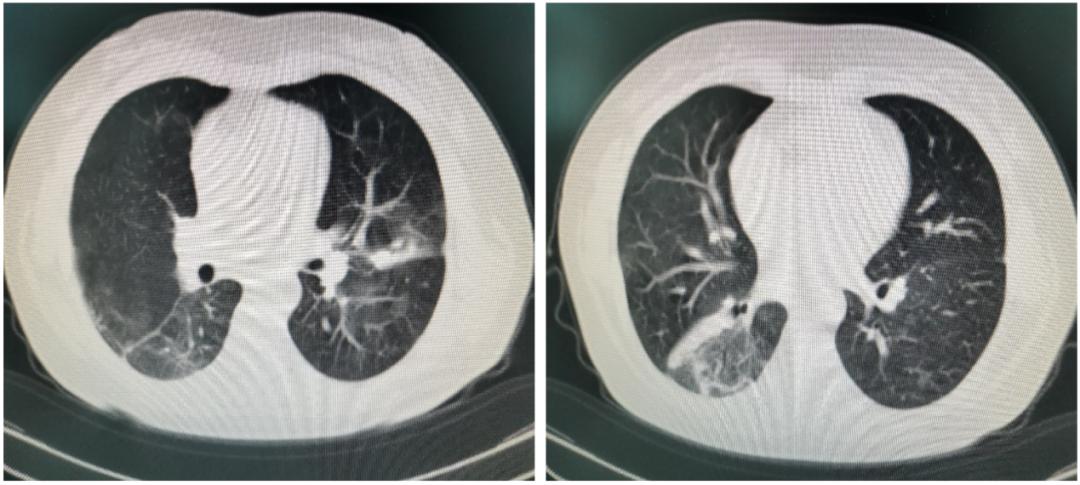

患者经超声支气管镜活检病理结果确诊为隐源性机化性肺炎。我们给予甲强龙40mg iv q12h,1周。1周后复查胸部CT提示病灶明显吸收(图3),无发热,咳嗽、气短减轻。体格检查听诊双肺未及湿啰音。为了防止病情反复出院后给予口服醋酸泼尼松40mg qd。

图3. 激素治疗一周后,双肺病灶范围较前缩小